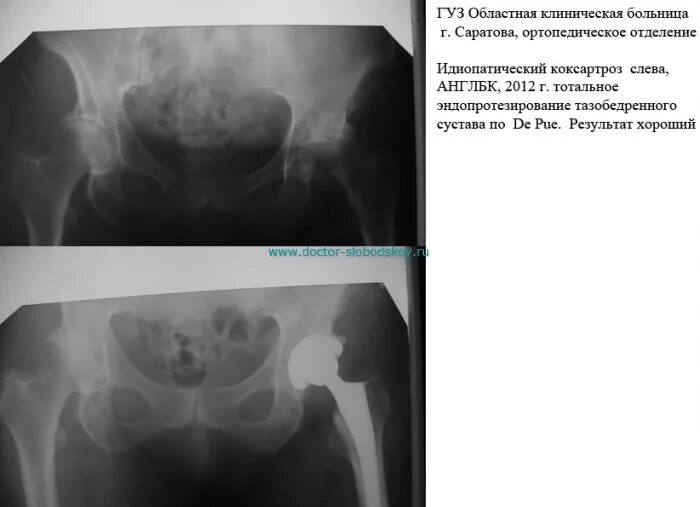

Коксартроз тазобедренного 3 степени операция